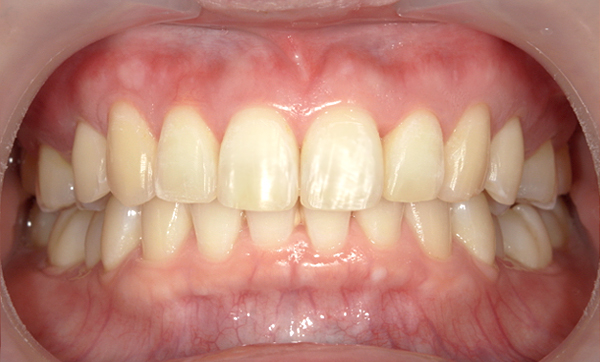

症例_006 「出っ歯」症例

治療期間:1年2ヶ月金額:54万円+税40代女性出っ歯捻転歯